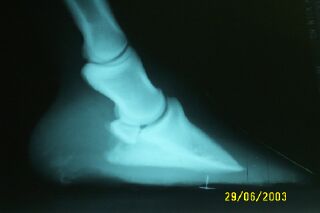

Posted on Wednesday, Jul 2, 2003 - 10:04 pm: Dr. O - here are Sparky's feet after being shod today - we did not use aluminum but did really bevel the inside edge for no contact with the sole. He will be reshoe in 5 weeks for further correction. I think getting the exrays was an important part in the toe reduction as we could see exactly where the toe had to be. We measured it to keep the proper distance. He trotted out much better and it was really hard to tell if he was off or not. Thanks for the advise. My farrier was saying that she was told at a recent clinic with Bob Marshall that they do not want to use eggbar shoes anymore for this type of problem or with laminitis. Have you heard anything on this? and that we should -short shoe- him on the heel - we did not short shoe at this point as my vet recommended bringing the shoe right to the end of where the heel should be and we decided to do it this way for a few shoeings then see what they look like. Thanks Janet![]()

Posted on Thursday, Jul 3, 2003 - 7:14 am: If the horse is standing square then the heel is a little low still but otherwise this is a great improvement.DrO |